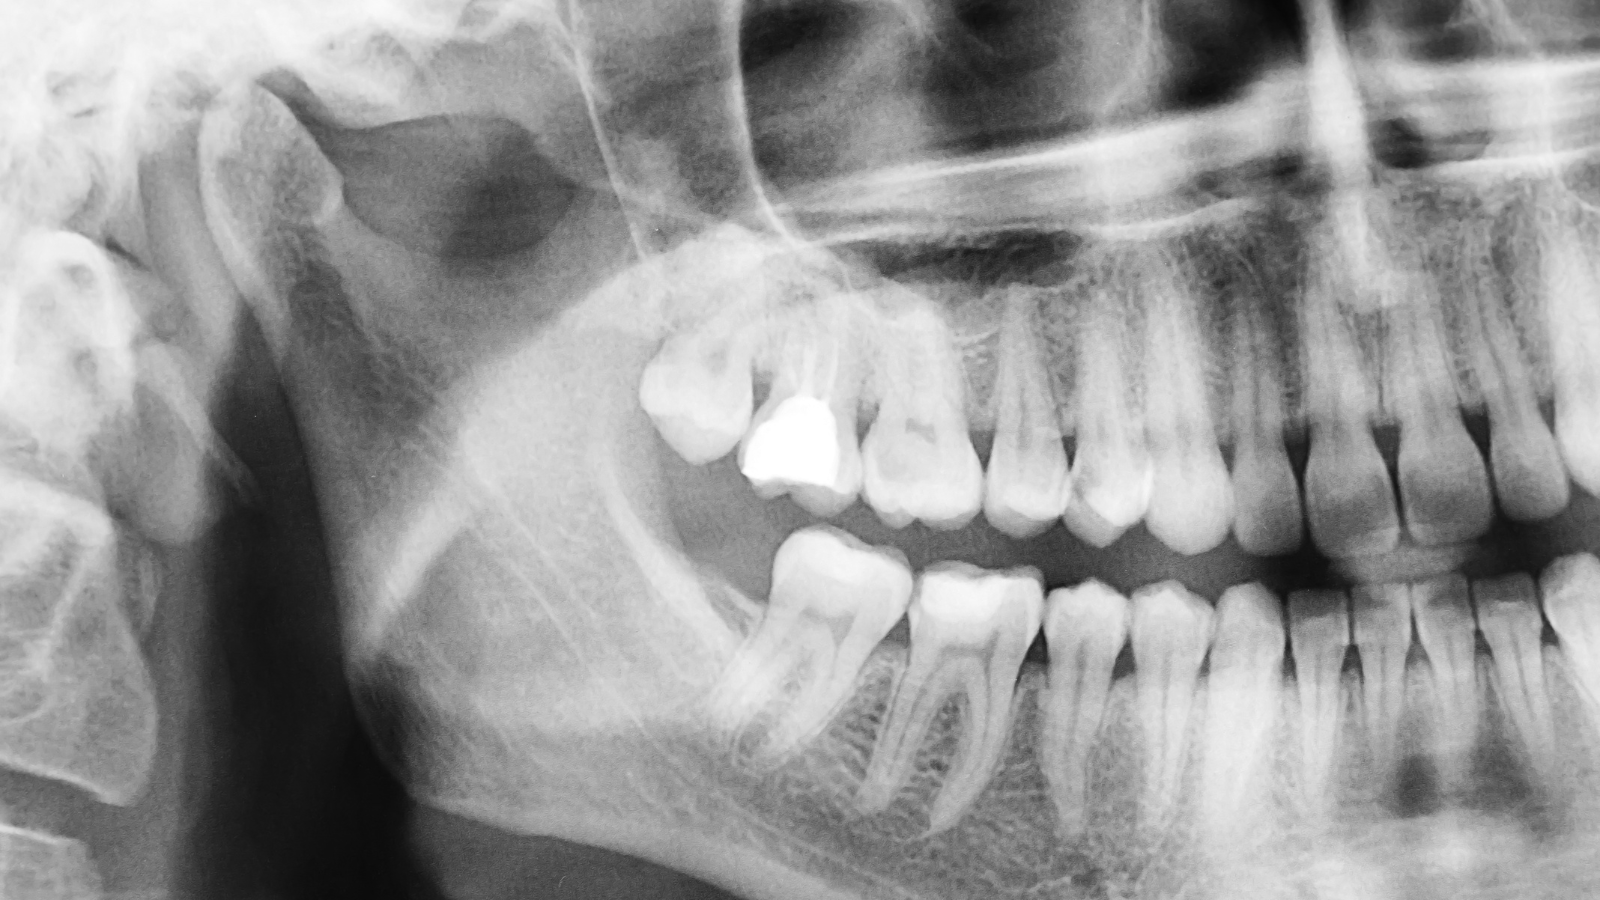

一般的な歯科医院では、初診時にパノラマレントゲン(お口全体を撮影する大きなレントゲン)や、デンタルレントゲン(歯を数本ずつ撮影する小さなレントゲン)を撮影します。

パノラマレントゲンは、上下の歯全体と顎の骨を一度に撮影できるレントゲンで、保険診療では約400点(約4,000円)、3割負担で約1,200円程度です。

虫歯の有無や親知らずの状態、顎関節の異常などを広範囲に確認できるため、初診時によく使用されます。